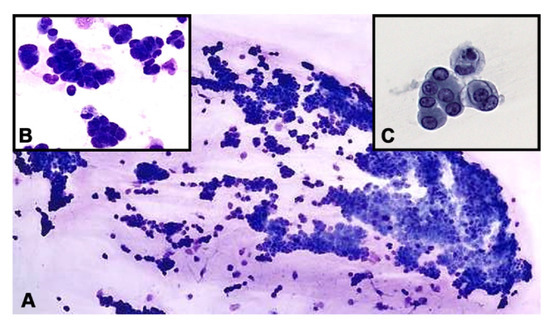

Microscopically, sheets of malignant epithelioid cells forming three dimensional groups were identified in the vitreous. Some groups appeared to form micropapillary structures with enlarged, hyperchromatic, eccentrically located nuclei with small nucleoli and a moderate amount of cytoplasm (Figure 2). Immunohistochemical studies were performed with appropriate positive controls, encompassing anti-cytokeratin cocktail AE1/AE3 (mouse monoclonal antibody; 1:100–1:500 dilution range; Cell Marque, Rocklin, CA, USA); PAX8 (mouse monoclonal antibody; 1:50–1:200 dilution range; Cell Marque, Rocklin, CA, USA), CD20 (mouse monoclonal antibody; 1:250 dilution; ThermoFisher Scientific, Riverside, CA, USA), CD3 (mouse monoclonal antibody; 1:10–1:20; ThermoFisher Scientific, Riverside, CA, USA), RCC (Human clear renal cell carcinoma antibody, mouse monoclonal antibody; 150–200 microliter; ThermoFisher Scientific, Riverside, CA, USA), SOX10 (rabbit polyclonal antibody; 1:25–1:100 dilute; Cell Marque, Rocklin, CA, USA) and S100 (mouse monoclonal antibody; 1–2 mg/mL; ThermoFisher Scientific, Riverside, CA, USA). All antibodies and testing were performed in a CLIA-certified laboratory.

Figure 2. (A). Hypercellular vitreous fluid demonstrating sheets of cohesive malignant epithelioid cells (Diff-Quik stain. Original magnification ×100). Inset (B). Groups of tumor cells forming micropapilla-like structures (Diff-Quik preparation, ×400). Inset (C). Pap-stained smear depicting clusters of neoplastic epithelioid cells with eccentric nuclei and vacuolated cytoplasm (original magnification ×400).